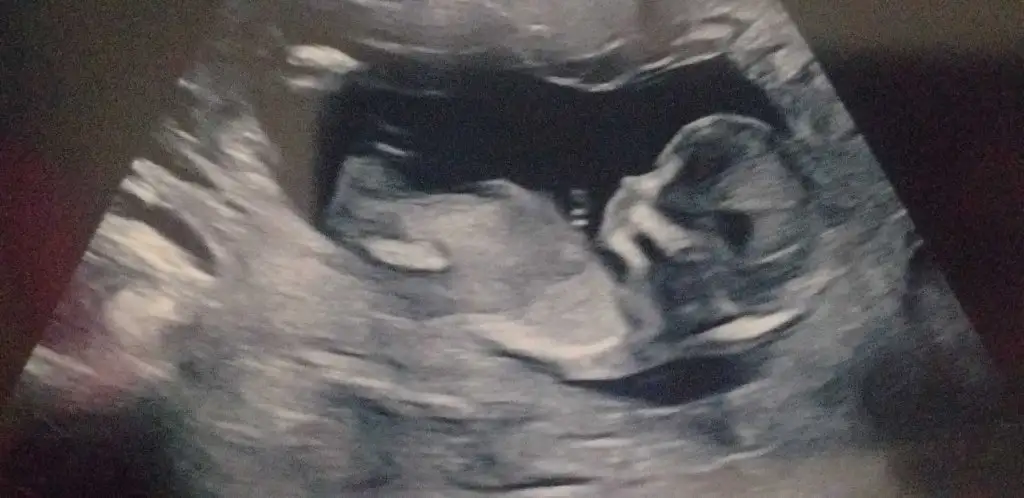

terzi söküğünü dikemez hesabı ben bir şey diyemiyorum bakın sizce bu yatay duran pipimi 😄

Eklentiler

• IMG_20220507_174503_edit_61742876382244.webp

IMG_20220507_174503_edit_61742876382244.webp

10,9 KB · Görüntüleme: 82